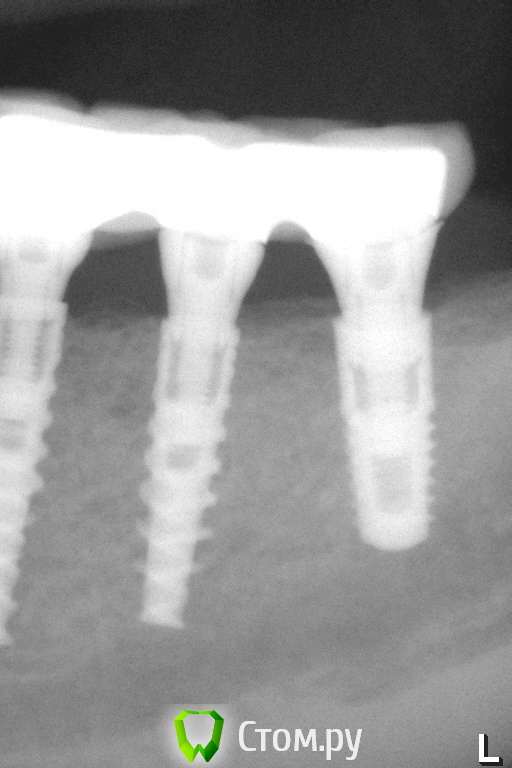

Pavel-Pskov Опубликовано 4 ноября, 2014 Автор Поделиться Опубликовано 4 ноября, 2014 Еще пара снимков.Через год. Ссылка на комментарий

АнтонТЛТ Опубликовано 4 ноября, 2014 Поделиться Опубликовано 4 ноября, 2014 Какие-то странные абатменты, как-будто в имплантаты заходят на 1мм. Ссылка на комментарий

АнтонТЛТ Опубликовано 4 ноября, 2014 Поделиться Опубликовано 4 ноября, 2014 в стартовом сообщении абатменты нормальныеНу там другой кейс)На втором, как будто один трансфер не по размеру у среднего имплантата, конуса не видно просто фаска-углубление. Там не видно и переключения платформы у трансфера.А если сравнивать абатмент у дистального и мезиальных имплантатов, то разница видна Ссылка на комментарий

Pavel-Pskov Опубликовано 6 ноября, 2014 Автор Поделиться Опубликовано 6 ноября, 2014 Ну там другой кейс)На втором, как будто один трансфер не по размеру у среднего имплантата, конуса не видно просто фаска-углубление. Там не видно и переключения платформы у трансфера.А если сравнивать абатмент у дистального и мезиальных имплантатов, то разница виднаДистальный 3,8. Ссылка на комментарий